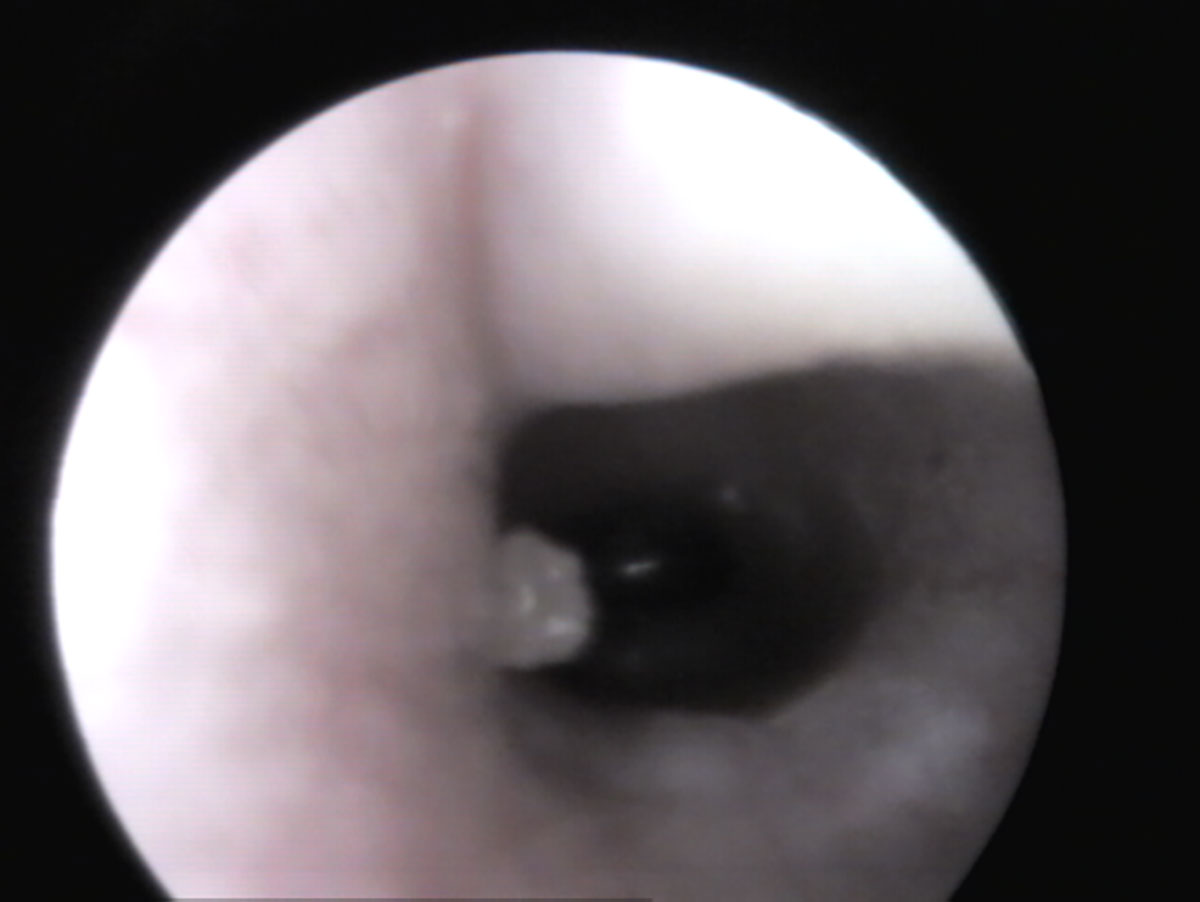

Fig. 3: Vista del timpano (pars tensa – trasparente, pars flacida – tessuto) di un coniglio

Fonte: J. Hein

In un orecchio sano, tirando delicatamente il padiglione auricolare verso l’alto (Fig. 1), si riesce solitamente a vedere fino al timpano (Fig. 3). Se è presente materiale nel condotto uditivo, è importante distinguere se si tratta “solo” di cerume accumulato (bianco in profondità, giallastro verso l’orifizio) e il condotto uditivo è altrimenti normale, oppure se sono presenti segni di infiammazione (arrossamento, gonfiore, lesioni, liquefazione del secreto) (Fig. 4) e possibili cause primarie come corpi estranei e/o ectoparassiti.